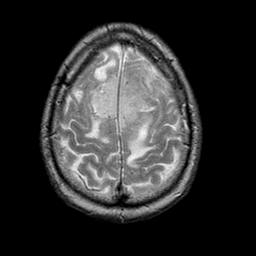

Meningioma, MR Study #1 -- Slice #17

[Home][Help][Clinical] Slice 17